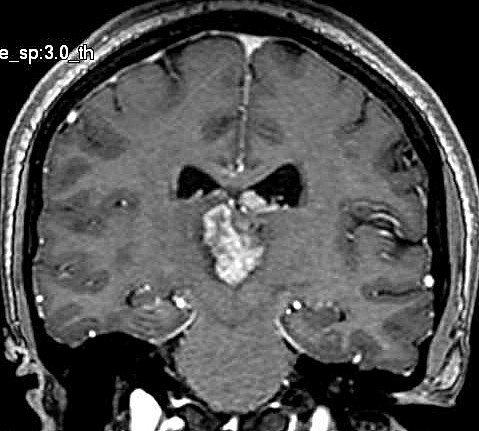

| Fem. 17a. |

| Nódulo sólido homogêneo preenchendo o III ventrículo, com limites precisos, com hipossinal em T1 e hipersinal em T2 e FLAIR, que se impregna por contraste paramagnético. Lesão menor implantada no assoalho do IV ventrículo provavelmente representa disseminação por via liquórica. |

| CORTES AXIAIS, T1 COM CONTRASTE | ||

| F. 17a. Tumor teratóide rabdóide atípico de III ventrículo. RM | HE | VIM, GFAP | HHF35, desmina, 1A4 | AE1AE3, EMA |